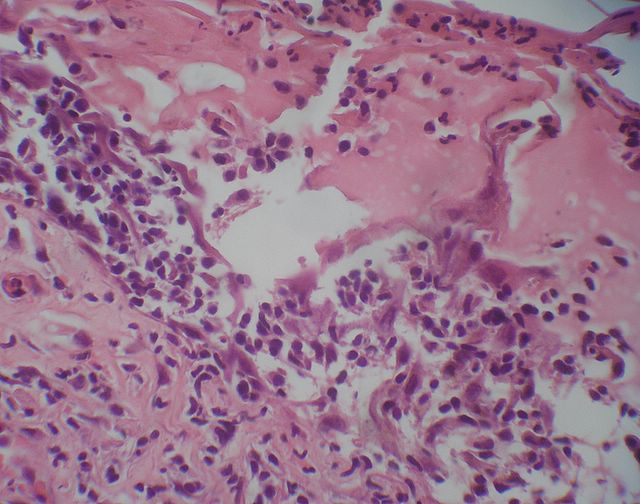

105 -- p9120004.jpg